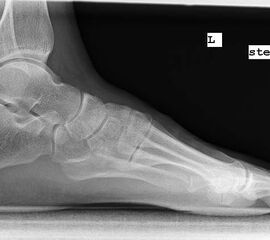

Röntgenaufnahme des Fußes im Stehen im dorsoplantaren und seitlichen Strahlengang (Abb. 1a-b).

Beurteilung des ersten Intermetatarsalwinkels (IMA), des Hallux valgus Winkels (HVA), des distalen (Distal Metatarsal Articular Angle, DMAA) und proximalen Gelenkflächenwinkels der Grundphalanx (Proximal Phalangeal Articular Angle, PPAA).

Abbildung 1a

Abbildung 1b